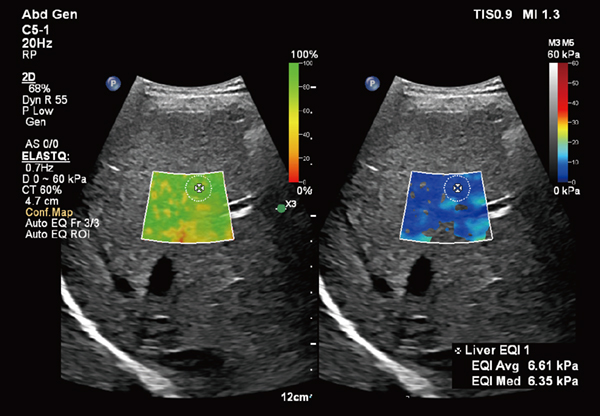

shear wave elastographyを使用して肝臓の硬さを非侵襲的に計測するアプリケーション「ElastQ(エラストキュー)」に,自動化機能が追加された(図1)。「Auto ElastQ」は,計測に適したフレームやROIポジションを自動で判別し,計測結果を表示することが可能である。これにより,これまで課題であった検査時間を最大60%短縮し2),99%の再現性であることが報告されている3)。

図1 Auto ElastQによる肝硬度の自動計測

適切なフレームとROIポジションが自動で判別され,計測が行われる。